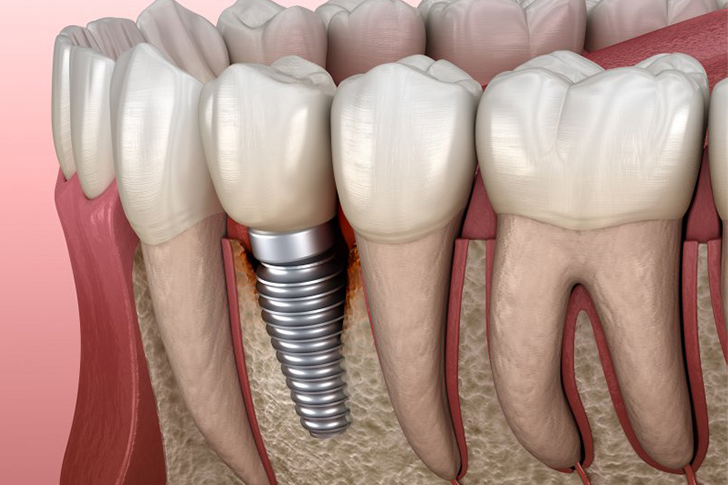

Dental implants are artificial tooth roots made of biocompatible materials, typically titanium, that are surgically placed into the jawbone. They serve as a stable foundation for replacement teeth, such as crowns, bridges, or dentures.

Osseointegration is a critical process in dental implant success. It refers to the biological bonding between the titanium implant and the surrounding jawbone. This process is essential for the stability and longevity of the implant.

Dental implants and crowns, supported by the process of osseointegration, offer a reliable and effective solution for restoring missing or damaged teeth. Understanding these components can help patients make informed decisions about their dental health. If you are considering dental implants or crowns, consult with a qualified dental professional to discuss your options and develop a personalized treatment plan. With proper care, dental implants can provide a long-lasting and functional solution to enhance your smile and improve your quality of life.